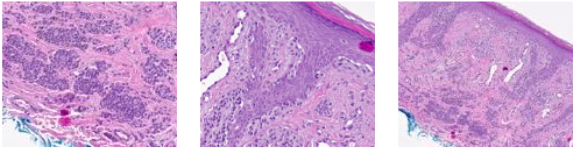

Lesion showed compound proliferation of melanocytes. In the epidermis, there were also many single melanocytes with limited pagetoid scatter. In the dermis, there were many nests, cords, and small syncytia with maturation or pseudo-maturation. Scattered inflammation was apparent. PRAME expression was absent. Due to the difficulty of the case and suspicious features, outside consultation was requested. p16 staining was performed and was diffusely positive. Neither PRAME nor p16 staining demonstrated biphasic reactivity as can be seen in the setting of melanoma. The consulting pathologist's impression was that the lesion was an extreme compound acral melanocytic nevus. No treatment recommendation was provided.

Even after an extensive workup with additional ancillary testing and a second opinion consultation, the diagnosis was still borderline or uncertain and diagnostic GEP was ordered to help eliminate this uncertainty.

DiffDx-Melanoma resulted in a gene expression profile consistent with a benign neoplasm.

By incorporating the results of the IHC stains, second opinion consultation, and DiffDx-Melanoma GEP results, a final diagnosis of atypical acral nevus was rendered. Given the benign diagnosis, the margins on the surgical excision were narrowed to 0.5 cm.